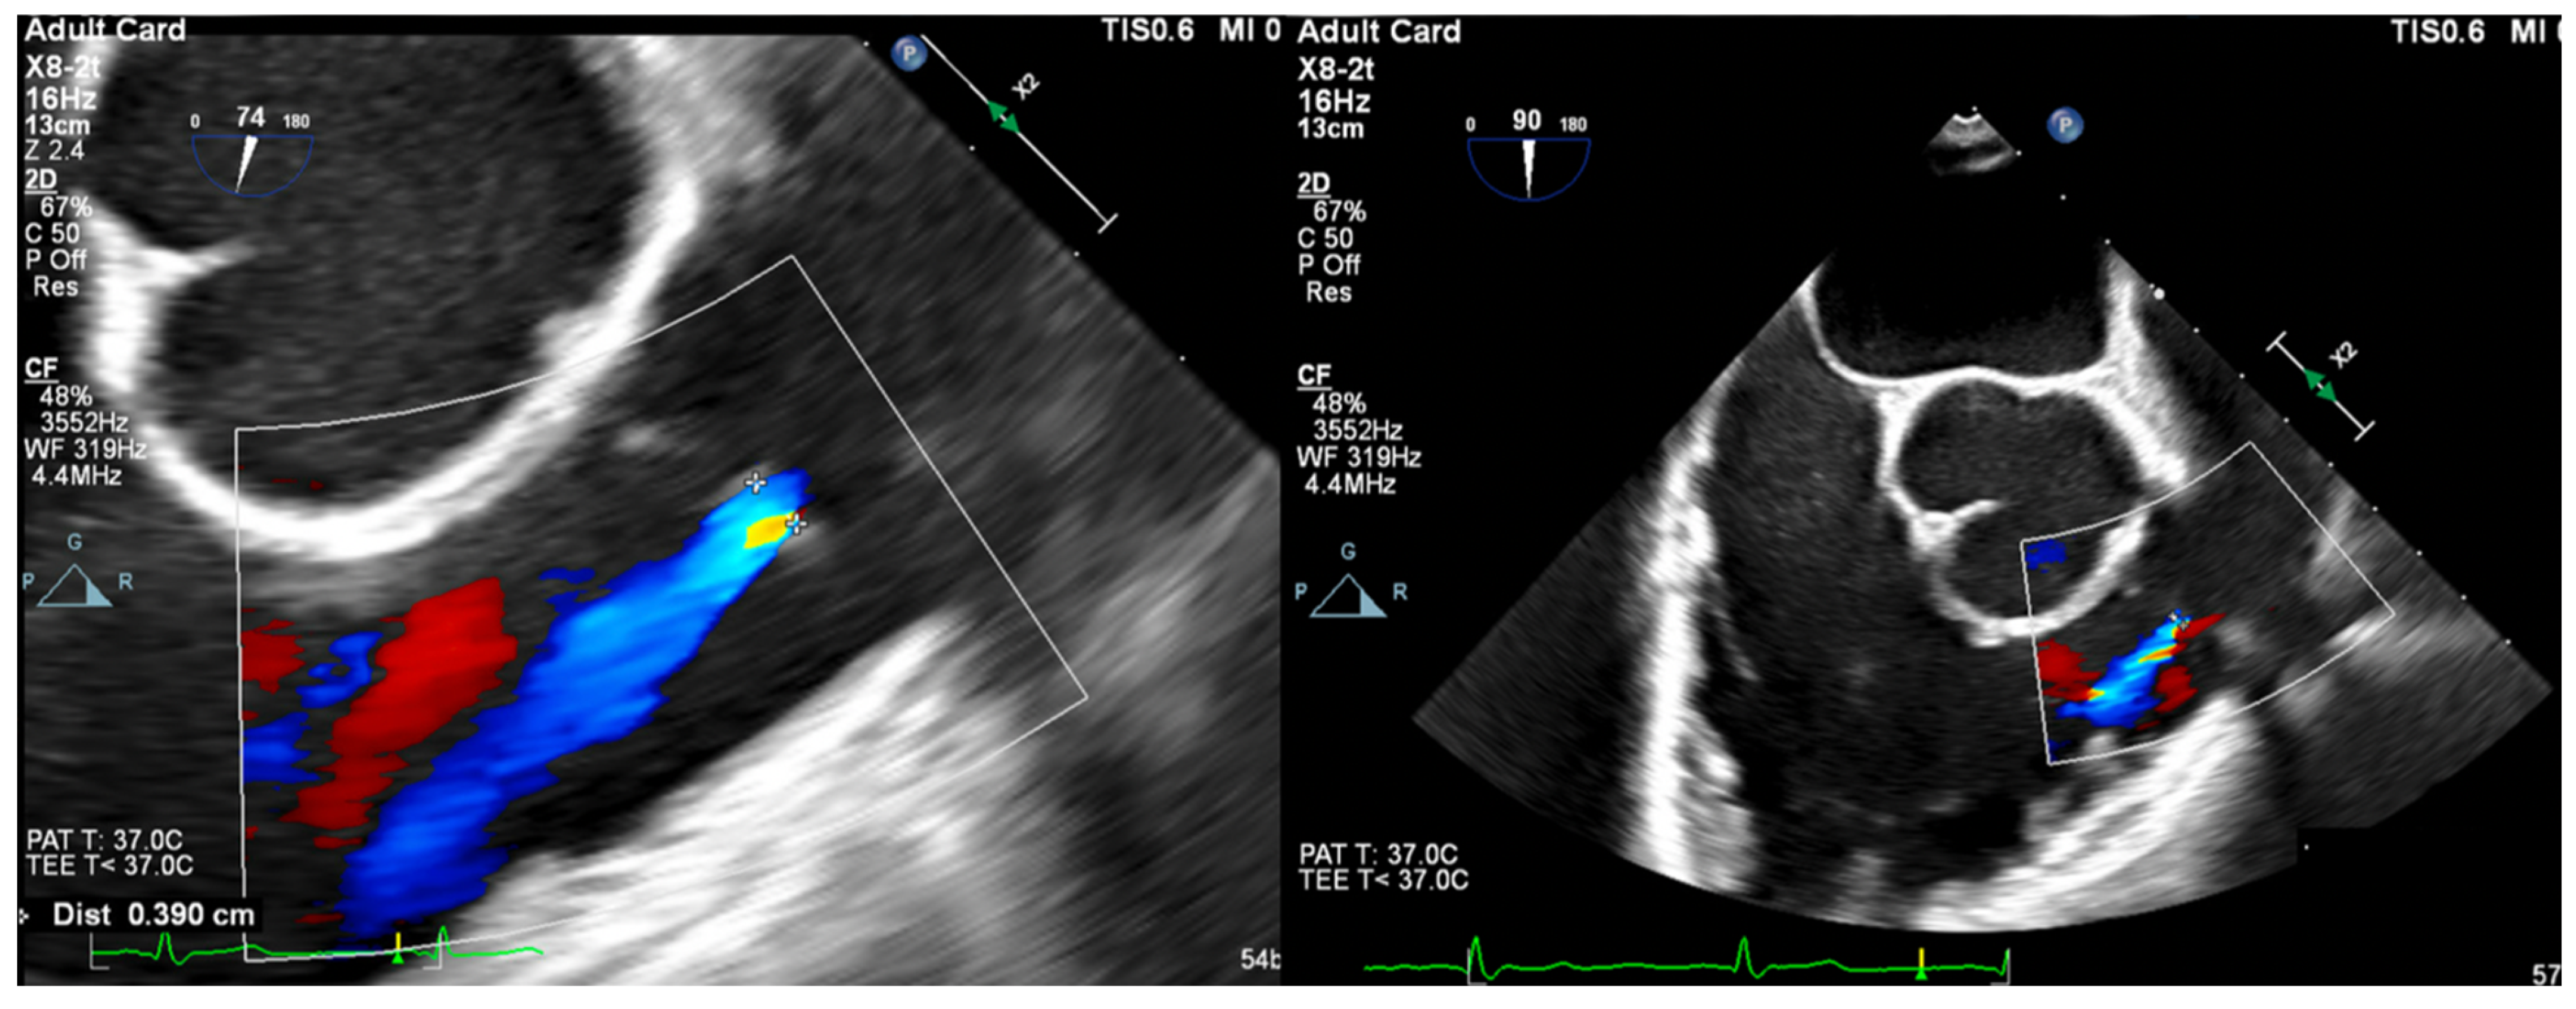

- Vena Contracta Width (VCW): Typically not used for multiple jets. Cutoffs for various grades of PR have not been validated, but most use AI cutoffs (Figure 1).

- VCW/PV ratio has been used with a value of >0.5 consistent with severe PR.